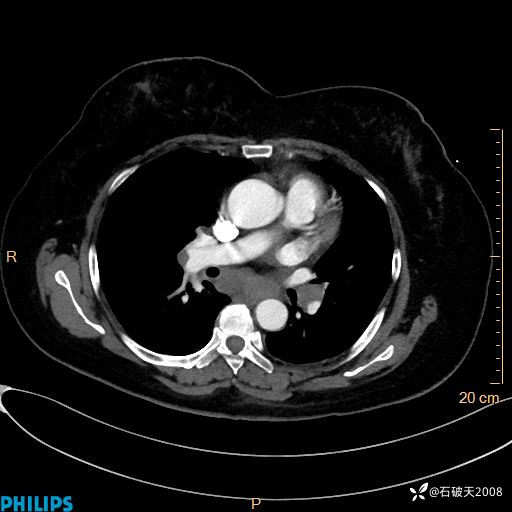

纵隔窗

静脉期